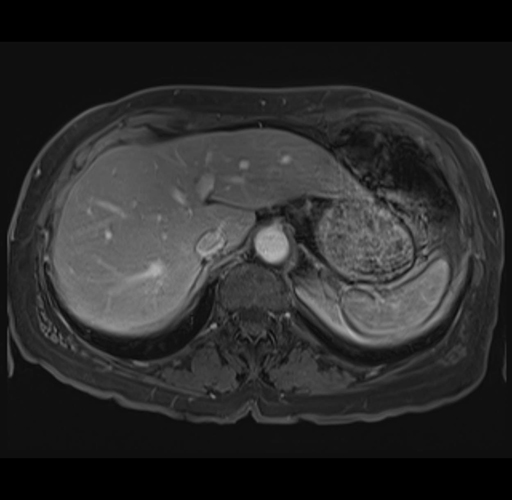

MRI T1

Imaging analysis